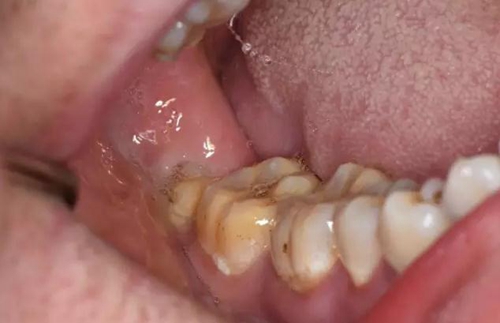

圖3.口內(nèi)檢查:48垂直阻生、有盲袋、牙冠萌出3/4,36、37牙齒健康。